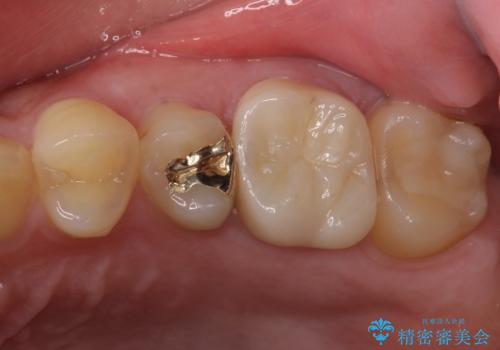

処置開始前から神経組織を部分的に除去する可能性が高いことが分かっていたため、ラバーダムなどの環境を整え、無菌的環境下にて処置を進めて行きました。

虫歯は深くまで進行しており、歯冠部後方の神経から出血が認められました。炎症を起こしている神経を除去したところ出血が治まったので、生体親和性の非常に高いセメントにて充填し、仮封をし、その日のうちに仮歯を装着しました。